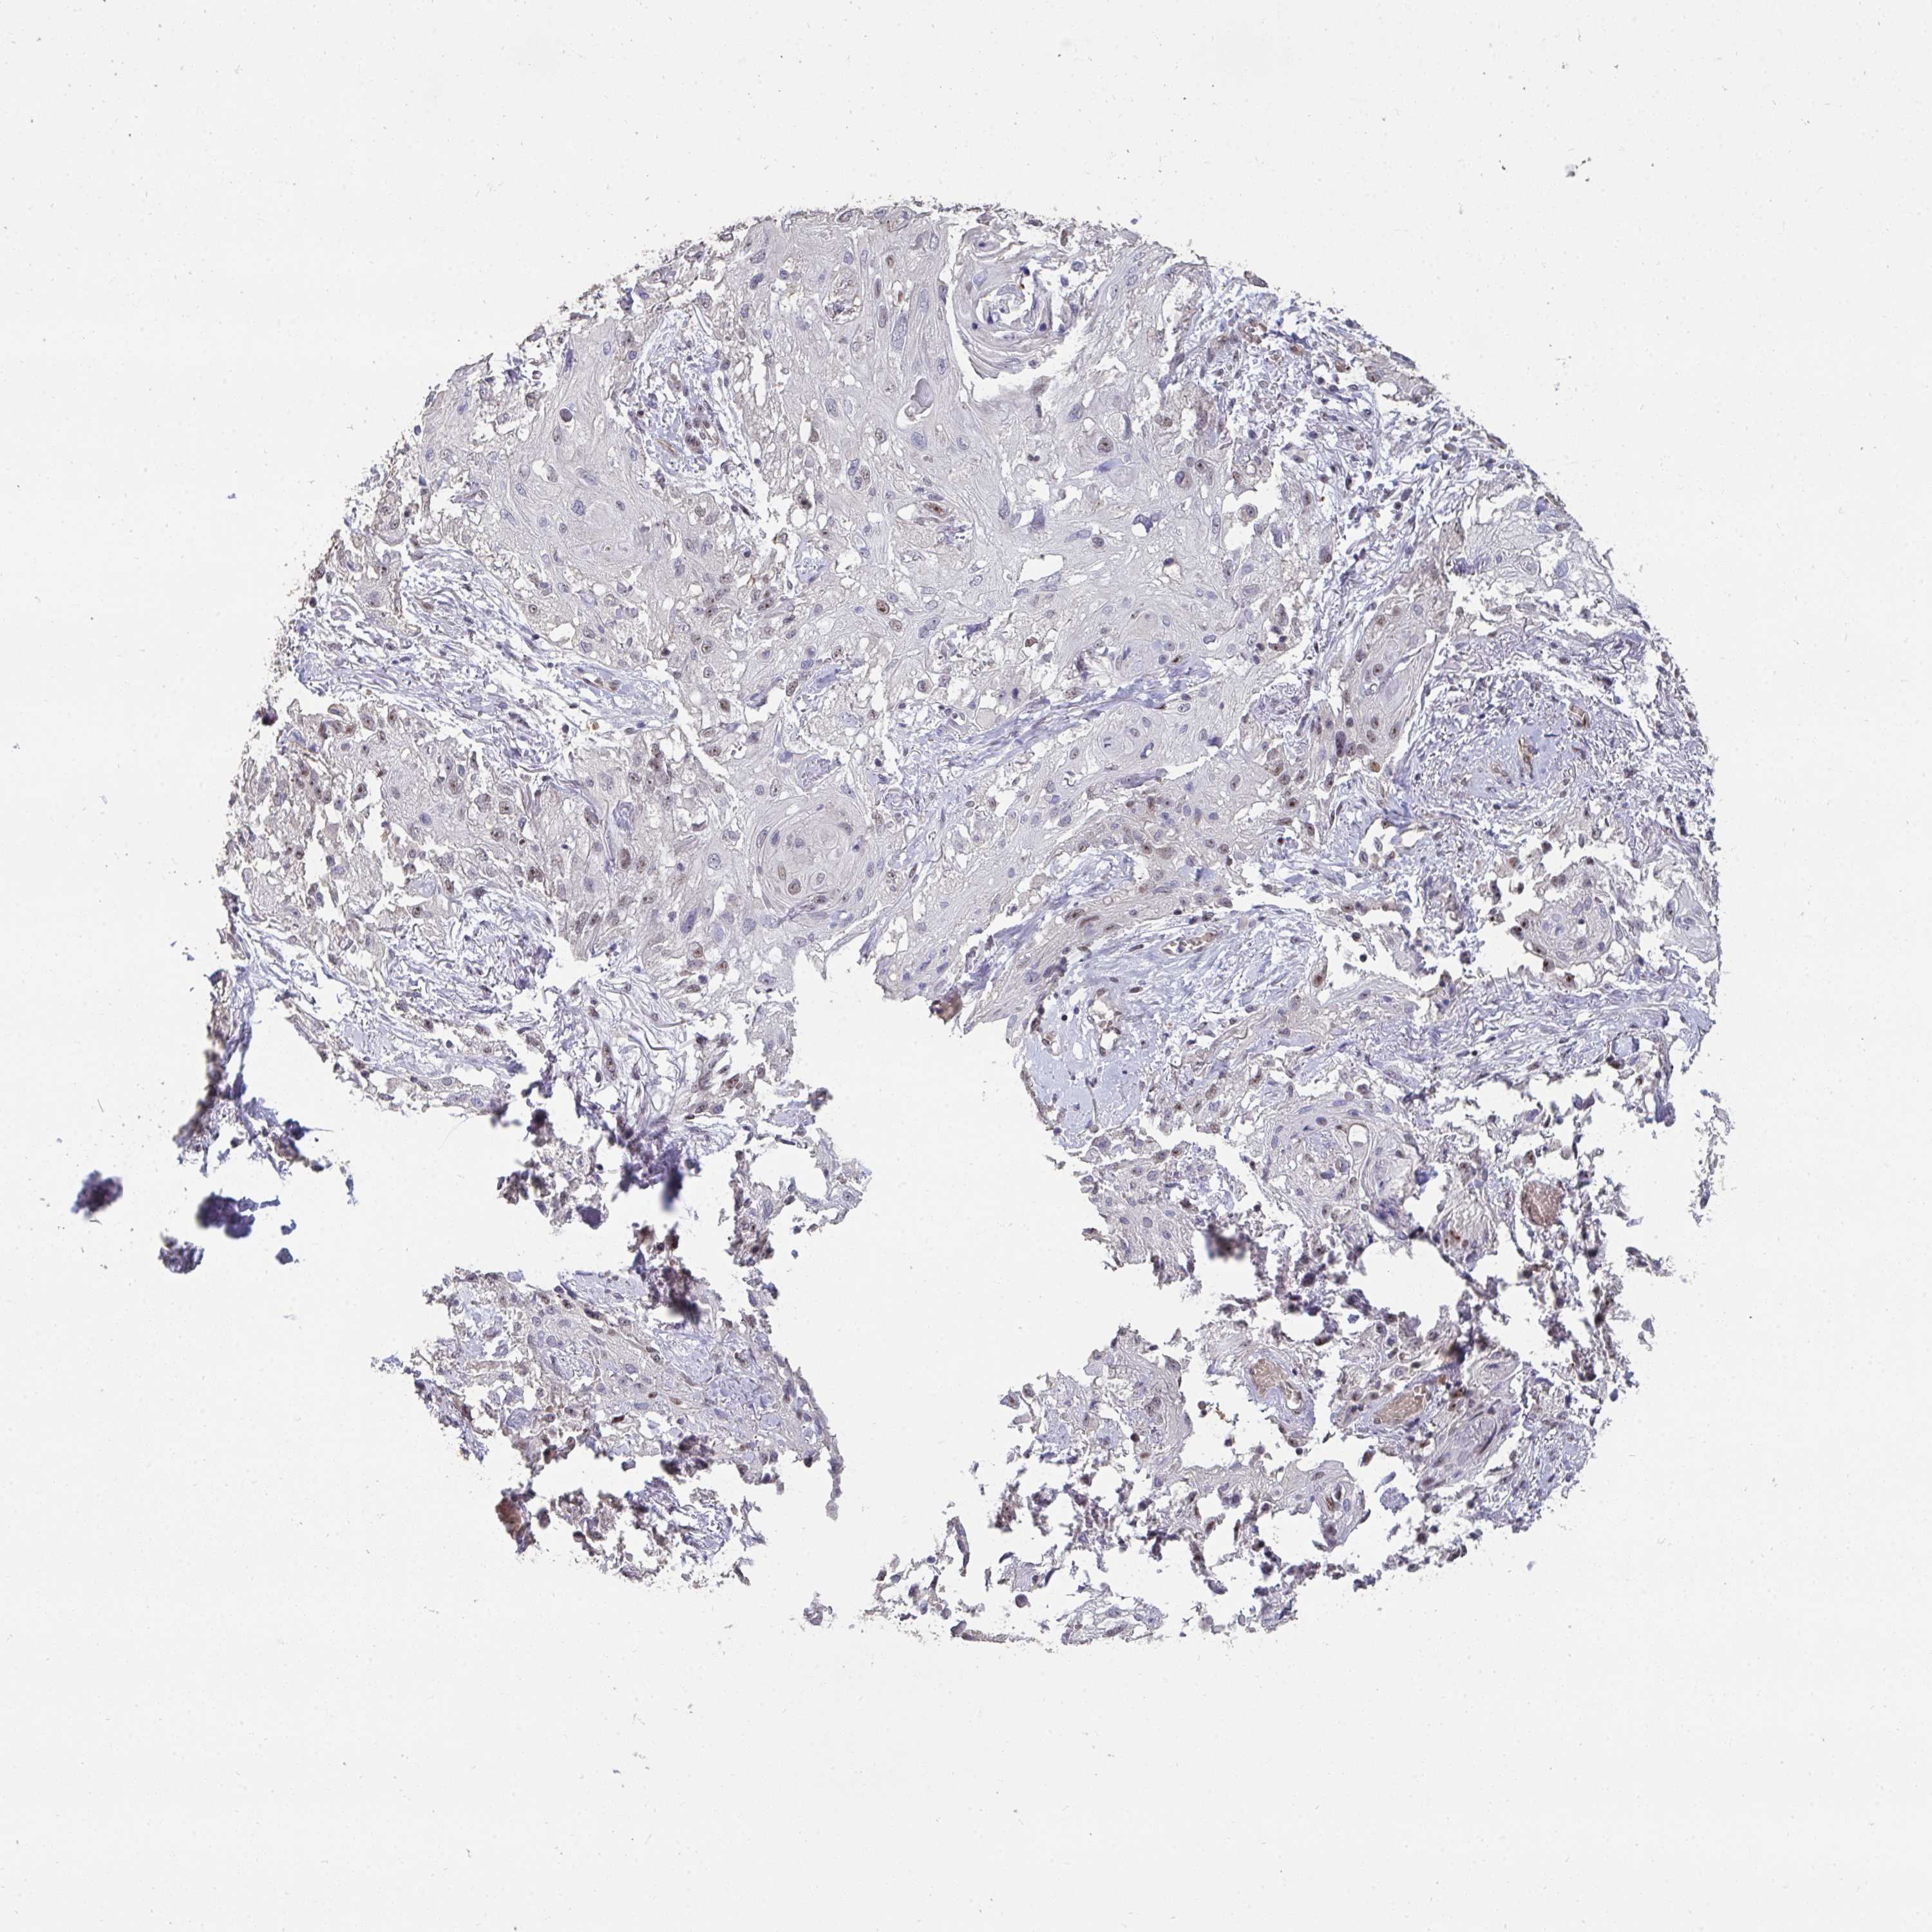

SKIN CANCER - Protein expressioni

A mouse-over function shows sample information and annotation data. Click on an image to view it in a full screen mode. Samples can be filtered based on level of antibody staining by selecting one or several of the following categories: high, medium, low and not detected. The assay and annotation is described here.

Antibody stainingi

Antibody staining in the annotated cell types in the current human tissue is reported as not detected, low, medium, or high, based on conventional immunohistochemistry profiling in selected tissues. This score is based on the combination of the staining intensity and fraction of stained cells.

Each image is clickable and will lead to virtual microscopy that enables deeper exploration of all samples and also displays staining intensity scores, fraction scores and subcellular localization as well as patient and tissue information for each sample.

Antibody HPA060290

Staining

High

Strong

Quantity

Location

Basal cell carcinoma

Squamous cell carcinoma, NOS